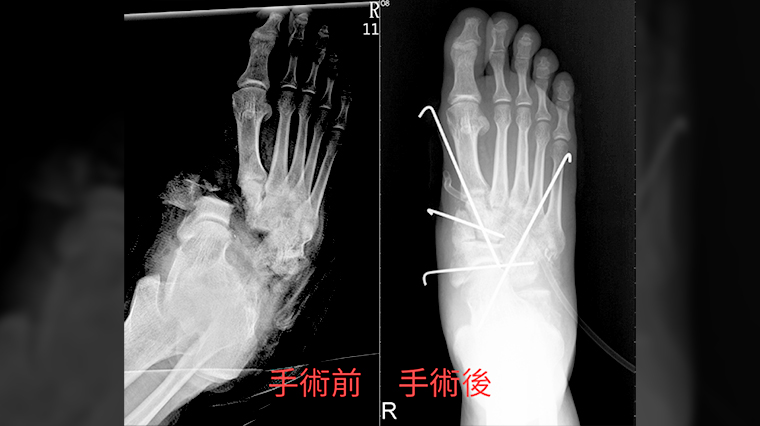

關於治療情況,王秋猛指出,為了防止細菌感染,醫護人員在幫吳男接回斷肢前,花費長時間把沾滿機油、砂石的傷口髒汙逐一剔除,手術時則在斷骨處先以4根骨釘固定,並依序縫補接回肌腱、神經、血管共10餘條組織;一旦骨骼接合錯位或肌腱血管神經對接錯誤,可能導致組織壞死,手術難度極高。

▲吳姓男子術前術後的x光照。(圖/羅東博愛醫院提供)